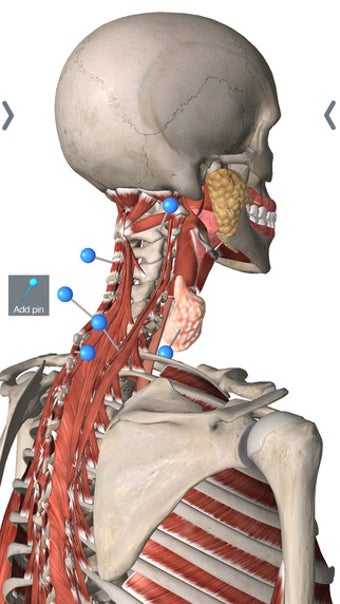

สำหรับนักศึกษาแพทย์โดยเฉพาะ Essential Anatomy เป็นเครื่องมืออ้างอิงที่ยอดเยี่ยม โมเดล 3 มิติช่วยให้คุณดูและตรวจสอบส่วนต่างๆ ของร่างกายมนุษย์ได้จากทุกมุม โดยให้รายละเอียดที่น่าทึ่งซึ่งปกติแล้วคุณจะสัมผัสได้ผ่านการผ่าเท่านั้น

Essential Anatomy ใช้งานง่ายมาก ฟังก์ชันการค้นหาคือสิ่งที่คุณต้องการมากที่สุดหากคุณกำลังเรียนอยู่ แม้ว่าคุณจะสนุกสนานไปกับการสำรวจและหมุนร่างกายก็ตาม คุณสามารถแยกชั้นของกล้ามเนื้อและเนื้อเยื่อออกเพื่อเผยให้เห็นสิ่งที่อยู่ภายใต้ ซึ่งจะช่วยให้คุณมีความคิดที่ดีขึ้นมากเกี่ยวกับการทำงานของร่างกาย มากกว่าที่จะอ่านมันในหนังสือ

นอกจากนั้น ยังมี เครื่องมือบุ๊กมาร์ก หากคุณต้องการบันทึกเฉพาะส่วนที่ต้องการย้อนกลับไปดูในภายหลัง และคุณสามารถแยกมุมมองร่างกายตามประเภทของชิ้นส่วน (เช่น กล้ามเนื้อ หลอดเลือดแดง เส้นเลือด ฯลฯ)